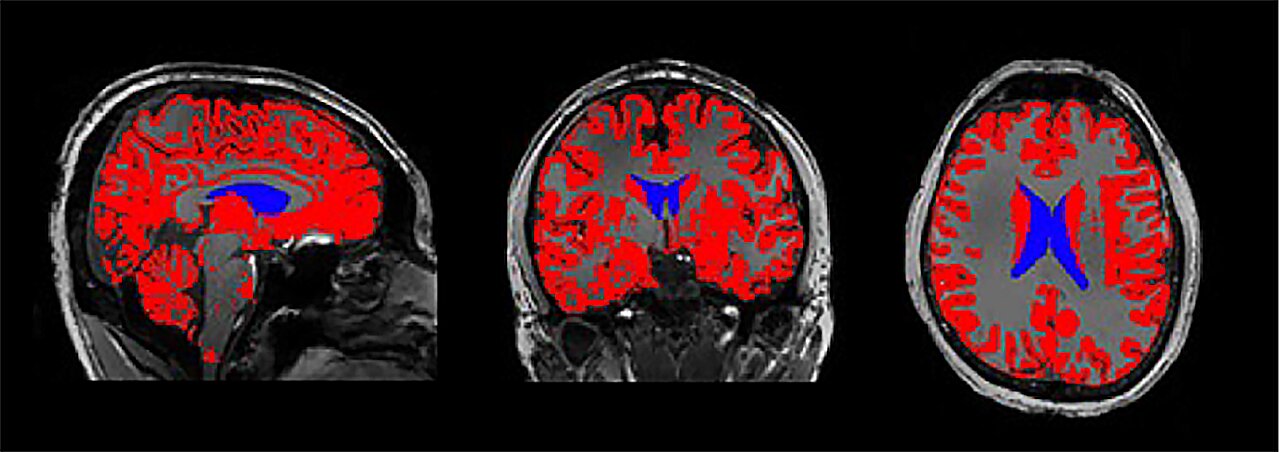

As volunteers slept inside the MRI, the researchers monitored two things simultaneously: the flow of cerebrospinal fluid and the slow, rhythmic brain waves characteristic of deep sleep. These slow waves are thought to reflect synchronized bursts of neural activity, when vast networks of neurons briefly turn on and off together.

The researchers suspect that these signals may reflect a complex mix of factors—perhaps small changes in surrounding brain tissues, shifts in pressure or volume, or subtle movements of the fluid as it circulates through the brain’s ventricles. Whatever the exact mechanism, the synchronization between deep sleep waves and CSF flow points to an intricate biological system evolved to keep our brains clean and healthy.